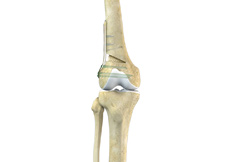

Total Knee Replacement

A Total Knee Replacement (TKR) or Total Knee Arthroplasty is a surgery that replaces an arthritic knee joint with artificial metal or plastic replacement parts called the 'prostheses'.

Patellofemoral Knee Replacement

Traditionally, a patient with only one compartment of knee arthritis would undergo a total knee replacement surgery. Patellofemoral knee replacement is a minimally invasive surgical option that preserves the knee parts not damaged by arthritis as well as the stabilizing anterior and posterior cruciate ligaments, ACL and PCL.